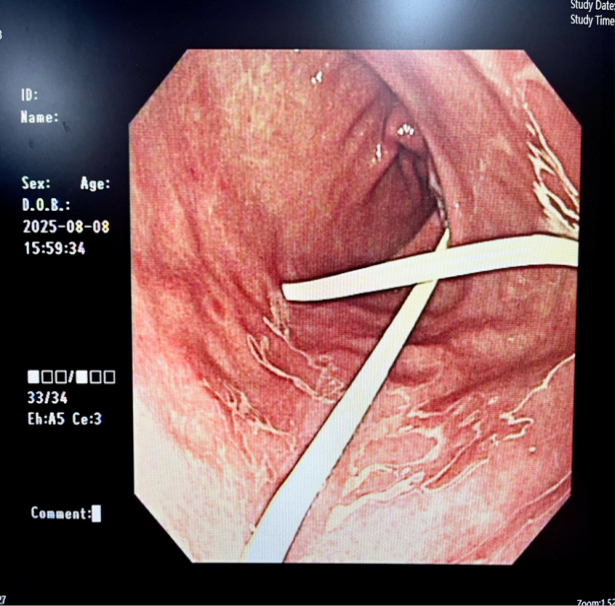

通过内镜技术实现“微创治疗”,医生将带有超声探头的内镜送入消化道(如胃、十二指肠),利用超声“透视”功能,精准定位囊肿位置,避开血管等重要结构,在消化道壁与囊肿之间“打一个小孔”,放入支架或引流管,让囊肿内的液体流入消化道,自行排出。

手术指证明确,消化内科医生团队在超声内镜引导下为患者行EUS(超声内镜)引导下胰腺假性囊肿引流术。3日后患者顺利康复出院。